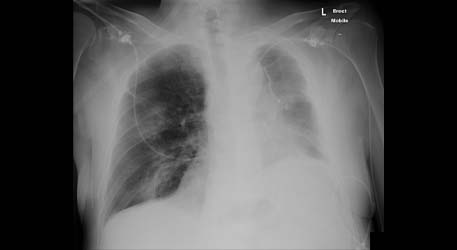

History: a 75 year old man status post partial left upper lobectomy, complicated by pneumothoraces status post chest tube placemente, presented with diffuse crepitus.

A chest radiograph was performed and is shown below. Radiographs: Diffuse subcutaneous emphysema and pneumomediastinum. Patchy basilar opacities In keeping with atelectasis and a probable small amount of left pleural fluid. Small biapical pneumothoraces

Chest CT: Extensive postoperative subcutaneous emphysema and pneumomediastinum. There is a moderate left-sided pneumothorax after left upper partial lobectomy, despite the presence o left chest tube with its lip at the left ape

Diagnosis: latrogenic subcutaneous emphysema